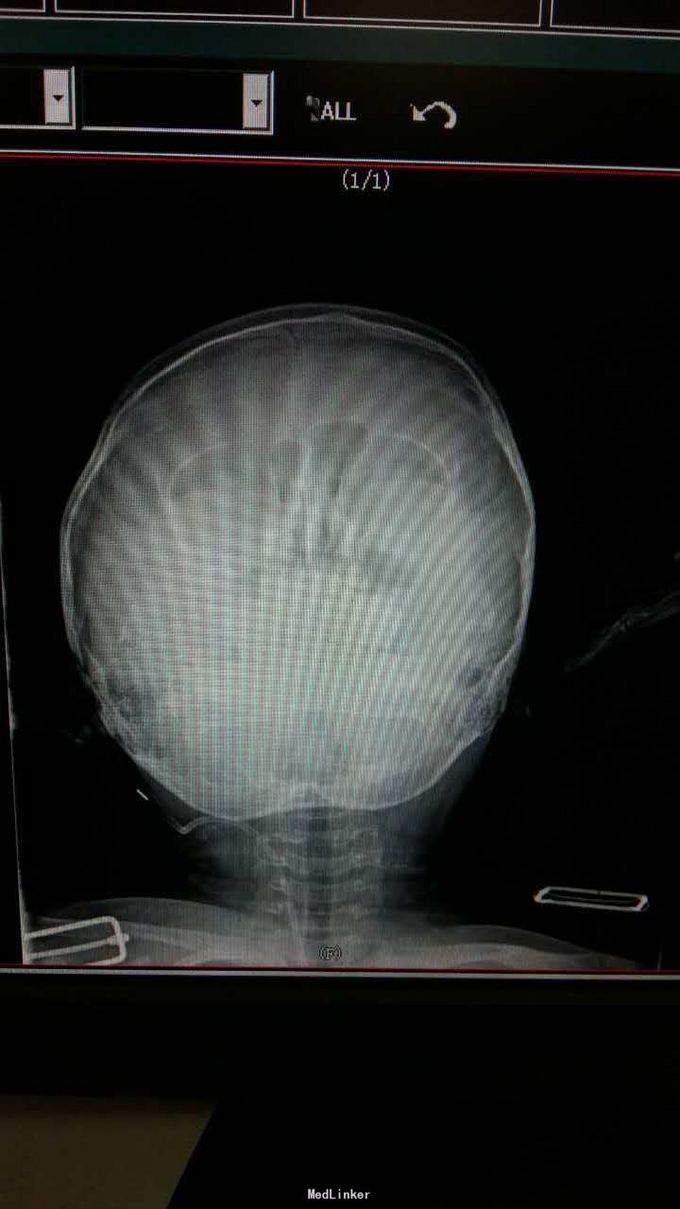

查体:发育正常,营养良好,被动体位,神志清楚,查体合作,头颅无畸形,前囟闭合,头围49cm,眼球正常,瞳孔等大正圆,对光反射灵敏,气管居中,双肺呼吸音清晰,心音有力,律齐,腹平软,肝、脾未触及。专科检查:大运动:竖头,翻身,坐,爬,走均能完成,但不会跑,独行时上身前倾,步基宽,双腿无屈曲,双足抬离地面不充分,不能走直线,不能单腿站,不能自行上下楼梯,有屈髋,但无屈膝,无尖足及交叉,能大把抓物,不能拇食指捏物,不会用勺子吃饭,只能拿笔乱画,能有意识的说单字,但会说的单字也较少,大约5个左右,认识亲人及常见的周围的物品名称,神经反射正常。 辅助检查:尿遗传代谢检查:甲基丙二酸尿症。